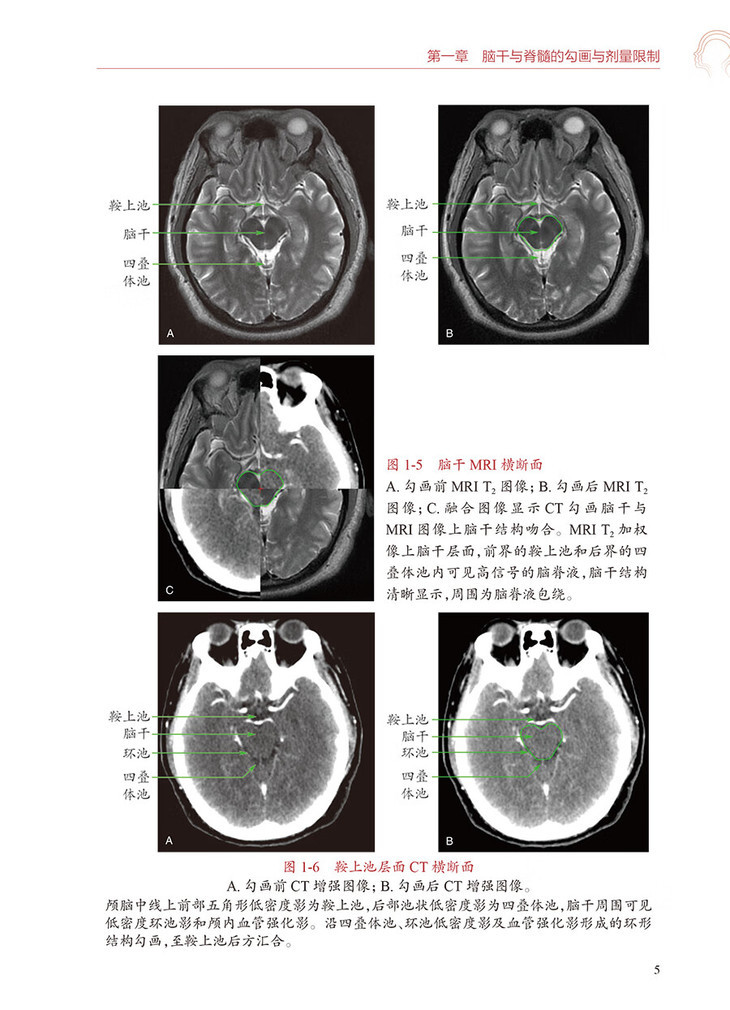

第二节勾画图谱/2